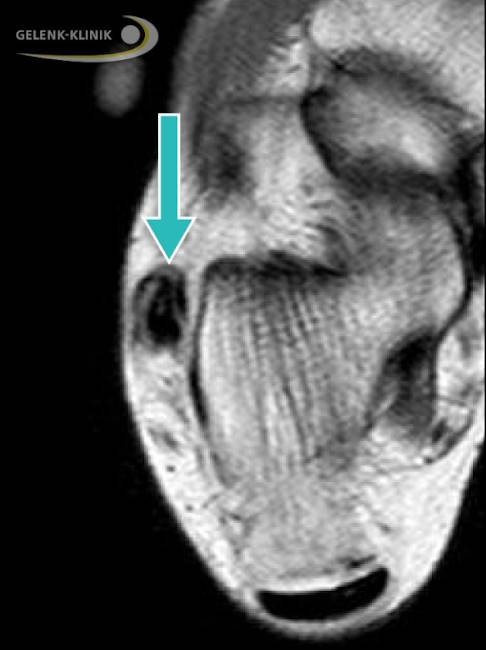

Eine Subluxation oder Luxation der Peronealsehnen bedeutet, dass sich eine oder beide Sehnen nicht so wie anatomisch vorgeschrieben in der knöchernen Gleitrinne befinden.

Bei der Subluxation verändert sich die Position der beiden Sehnen innerhalb der Gleitrinne, das darüber liegende Retinaculum bleibt jedoch intakt. Die Betroffenen berichten über ein spürbares Springen oder „Schnappen“ der Sehne am Außenknöchel bei Bewegung des Fußes. Dieses oft tastbare Schnappen kann durch eine kreisförmige Bewegung des Fußes ausgelöst werden. Manchmal treten Schmerzen auf. Die meist chronisch auftretenden Subluxationen sind z. B. anlagebedingt oder entstehen aufgrund einer nicht ausgeheilten akuten Luxation.

Die Peronealsehnenluxation ist eher ein akutes Geschehen. Dabei wird eine oder beide Sehnen aus ihrer Gleitrinne hinter dem Außenknöchel verschoben. Eine häufige Ursache ist die verletzungs- oder überlastungsbedingte Schädigung des über den Sehnen liegenden Haltebandes (Retinaculum). Die lange Peronealsehne neigt aufgrund ihrer anatomischen Lage eher zur Luxation als die kurze Peronealsehne. Begünstigend wirken eine flache oder konvexe Gleitrinne. Peronealsehnenluxationen sind meist Folge einer Verletzung, häufig betroffen sind Profisportler, darunter insbesondere Skifahrer. Peronealsehnenluxationen können zu erheblichen Beeinträchtigungen mit Unsicherheit beim Gehen und Stehen und zu Schmerzen führen.

Dabei hat die DVT mehrere Vorteile: Sie ist nicht nur strahlungsärmer als das konventionelle Röntgen. Mit ihr lassen sich dreidimensionale Bilder anfertigen, auf denen man die Knochenoberfläche, die Gleitrinne der Sehnen und eventuelle Knochenerhebungen gut erkennen kann. Häufig wird auch eine Kernspintomographie durchgeführt. Sie ermöglicht eine besonders gute Beurteilung der Sehne und des umliegenden Gewebes. Risse, Luxationen und Entzündungen der Sehne können damit gut unterschieden werden.